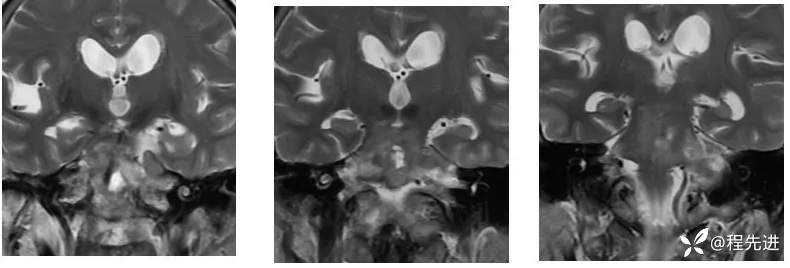

【现病史及既往史】:右眼斜视及视力下降7个月,右眼脸下垂3个月,右眼失明1个月

查体:生命体征平稳,右眼脸下垂,右眼失明,左眼内收位,外展受限,光反应迟钝,左侧角膜反射减弱,左侧听力下降,左面部痛温觉减弱无吞咽困难,无饮食饮水呛咳,伸舌舌尖左偏。